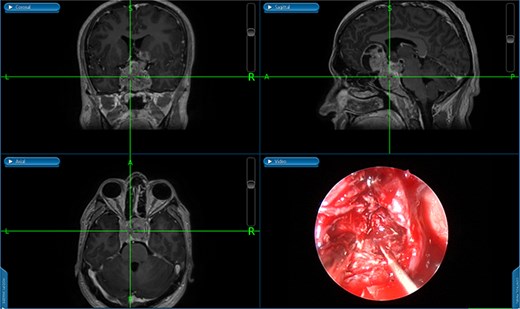

The initial evaluation included a brain magnetic resonance imaging (MRI), showing a small pituitary mass measuring 1.3 × 2.1 × 1.9 cm with suprasellar extension, neighboring the optic chiasm (Figs 1 and 2). Laboratory results revealed a high prolactin level of 110 ng/ml and normal thyroid function tests. A pituitary macroadenoma, specifically a prolactinoma, was presumed, and cabergoline was initiated.

A coronal brain MRI showing a heterogeneous, enhancing lesion located within the sphenoid sinus, extending superiorly to the sellar and parasellar regions. The mass shows irregular borders and appears to cause a mild compression of the optic chiasm.

A sagittal brain MRI reveals the same mass with superior extension to the sellar and suprasellar regions. The lesion is exerting a compression to the optic chiasm. The mass effect extends posteriorly toward the clivus, with irregular margins indicating invasive potential. Adjacent structures like the pituitary stalk appear to be displaced.